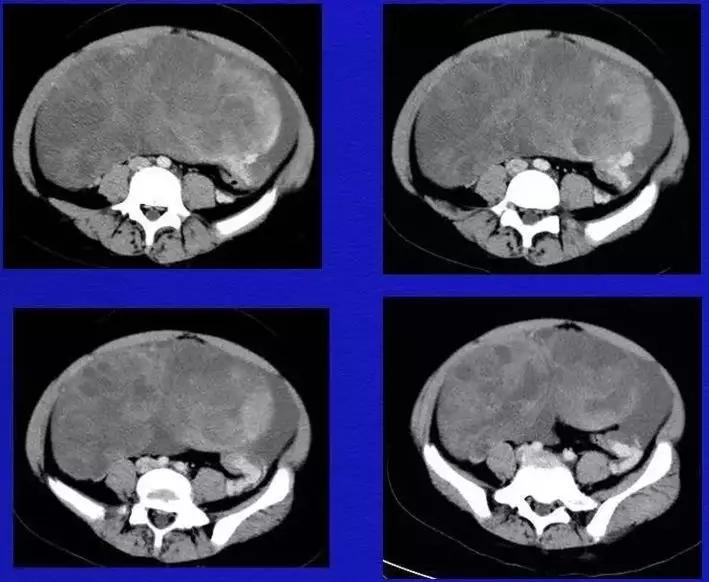

病例10

女,39 岁,体检发现盆腔肿块1月余

CA125:51U/ml

病理:左侧卵巢卵泡膜-纤维瘤